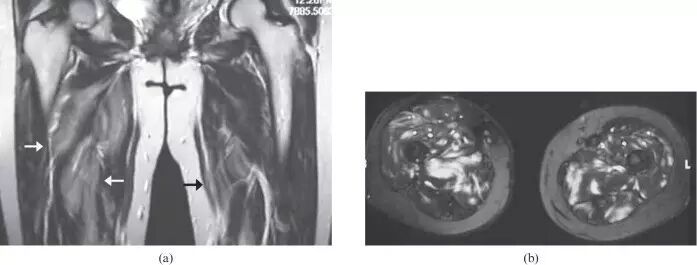

图8.26岁女性多发性肌炎,呈现双侧下肢疼痛和肌肉无力。(a)大腿的轴向T2加权的MR图像显示在股外侧肌,中间肌,内侧肌和股直肌(箭头)的异常,广泛的羽状水肿。注意保持正常的肌肉结构。T1加权成像(未显示)在受影响的肌肉中未显示信号改变或萎缩,或在此情况下有助于诊断。(b)两腿的冠状动脉脂肪抑制的T2加权的MR图像还在小腿的肌肉(箭头)中显示广泛的水肿信号。右腓肠肌的内侧头显得幸免(箭头)。

![]()